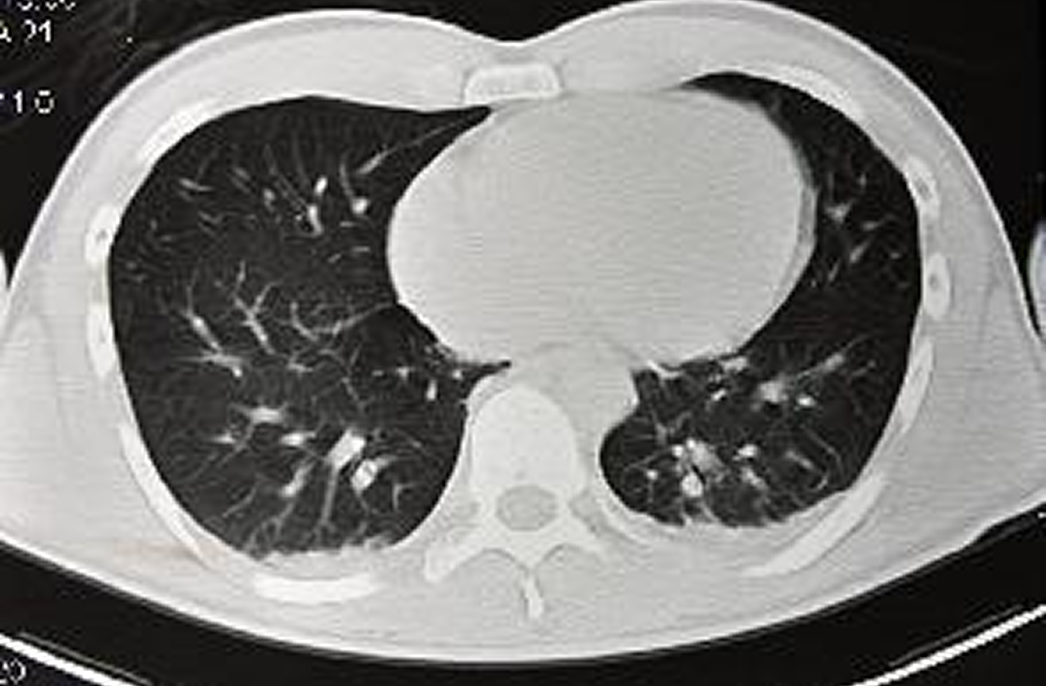

肺がんドック 死亡原因第一位の肺がんの早期発見に

肺がんの検査方法は、CT装置(日立社製Supria grande64chマルチスライスCT)での検査が適しています。

撮影時間は約5秒程度にも関わらず、胸部単純X線撮影だけでは発見できなかった腫瘍や、心臓、骨に隠れている腫瘍を発見することが可能です。